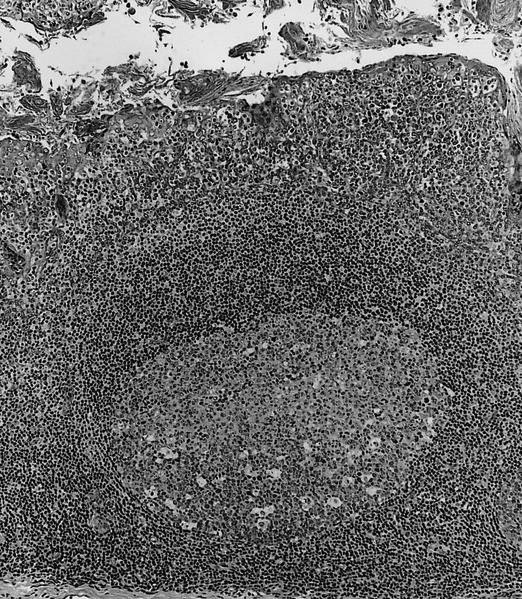

Normal lymph node

Primary follicle

Lymph node

Secondary follicle

Paracortical T zone